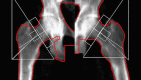

Phosphaturic mesenchymal tumors (PMT) are a rare neoplasm oftentimes associated with tumor-induced osteomalacia (TIO). The non-specific presentation and symptoms of these pathologies make them difficult to diagnose. We report a case of a 52-year-old patient with an intermetatarsal phosphaturic mesenchymal tumor who presented to the orthopedic sports medicine clinic with metabolic deficiencies and bilateral subtrochanteric cortical stress fractures indicative of osteomalacia. The tumor was entirely resected within nine months of symptom onset and has shown no recurrence at the one-year follow-up. This case report characterizes an unusual cause of stress fractures presenting to orthopedic sports medicine clinics and the variability in the presentation of phosphaturic mesenchymal tumors.